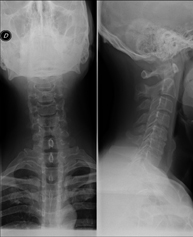

- Cervical spine X-ray

This technique uses X-ray rendered imaging for examining the cervical spine. Indicated for: trauma, cervical pain.

Técnica mediante la cual, utilizando rayos X, se obtienen imágenes de la columna cervical para su estudio. Indicaciones: traumatismo, contractura cervical, dolor articular. - RX Huesos propios nasales